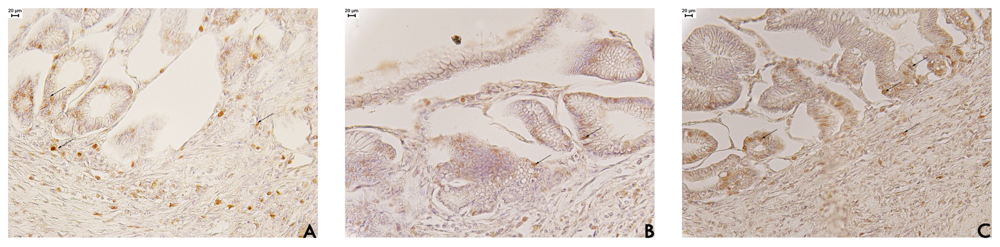

Cell proliferation plays a predominant role in wound healing, and PCNA (proliferation cell nuclear antigen) has been demonstrated to be a useful marker of cell proliferation. PCNA is an auxiliary protein of DNA polymerase, an enzyme necessary for DNA synthesis and cell proliferation. In the present study, factor related to tissue repair were examined in an attempt to gain information on the mechanism through which EAF affects ulcer healing. The results indicated that EAF stimulated gastric epithelial cell proliferation by enhanced expression of PCNA (Figure 3).

The positive PCNA immunohistochemical labeling in stomach tissue from EAF-treated rats appeared mainly at the base of the glands (Figure 3). This result occurs because stem cells re-organise at the base of glands, indicating the unidirectionality of cell proliferation, which is different in normal regions that have a bi-directional proliferation [20]. We also assessed the number of neutrophils in the region under the regenerative mucosa in stomach tissue from the three groups (Table 3). The cell counts showed a significant increase (p < 0.05) in neutrophils in regions under the regenerative mucosa for EAF (15.39 ± 1.52 cells/mm2) compared with the saline (6.40 ± 1.69 cells/mm2) or cimetidine (11.40 ± 0.93 cells/mm2) groups.